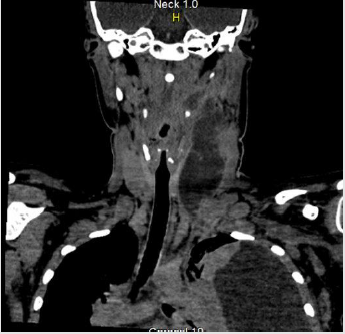

A chest radiograph showed large free left pleural effusion. Blood cultures were collected and Piperacillin-tazobactam was initiated for sepsis. The patient was submitted to computed tomography (CT) image of neck and chest that showed collection on the left side of neck spreading from the parapharyngeal space to the supraclavicular region. The left internal jugular vein could not be visualized because bulky collection was hindering it. Lung CT images showed up large left pleural effusion and multiple bilateral pulmonary nodular opacities, some excavated, with soft tissue density measuring 8 to 13mm, suggesting an embolic origin (Figure 1). Abdomen and pelvis CT demonstrated an unexpected iliopsoas abscesses, mainly on the right side. The patient was promptly submitted to needle aspiration of cervical mass and diagnostic thoracentesis, but later the exudative pleural effusion was drained. Doppler ultrasound of cervical mass and veins revealed thrombosis within left internal jugular vein. The patient proceeded to the operating room for neck and iliopsoas abscesses drainage. Cultures of neck collection, pleural effusion, iliopsoas abscesses and blood were carried out to detect common germs, fungi and mycobacteria. Despite the negative tests, classical clinical picture and the improvement with antibiotic were essential to make the diagnosis. Venous therapy was maintained for two weeks and oral therapy with metronidazole for complete six weeks. The young patient was discharged without residual disability.

The infection come up from the oropharyngeal and tonsils leading to septic thrombophlebitis and abscesses [1]. After the development of thrombophlebitis, haematogenous or lymphatic dissemination from peritonsillar vessels leads to impairment of the lung and pleura in over 90% of cases, followed by joints, skin, soft tissue and liver [4]. The most common symptom is sore throat and the most specific clinical sign of the syndrome is swelling or pain especially in the internal jugular vein territory, present in 52% of patients as occurred (Figure 2) [2]. Proper management of patients with suspected Lemierre syndrome is done by a high grade of suspicion, imaging studies, culture, long-term antibiotic therapy against Fusobacterium and drainage of collections when indicated [8]. As there is no consensus about antibiotic regimens, it is guided by expert’s experience, advising six weeks of therapy [4]. Thus, due to the Fusobacterium resistance to penicillin, commonly used antibiotics are: penicillin and beta-lactamase inhibitor, carbapenem, or in case of penicillin allergy, metronidazole [4,9]. Anticoagulation is controversial because of the lack prospective studies. When there is an neck surgery indication, the thrombosed vein should be removed [8].